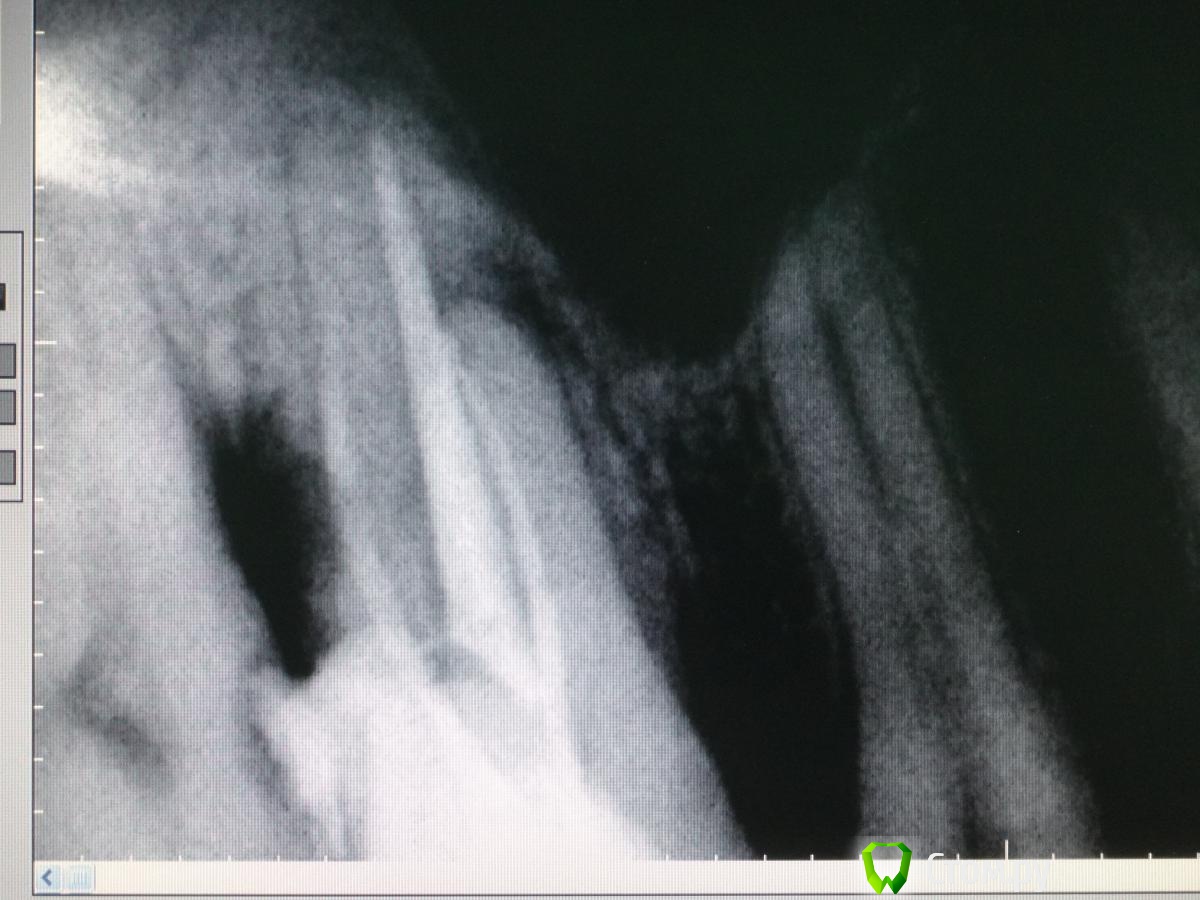

Slaggy Опубликовано 22 ноября, 2014 Автор Поделиться Опубликовано 22 ноября, 2014 (изменено) С "неаккуратным зубом" - откинул, заполировал, ушил, времянка. Фоткать некогда было, может на следующих этапах. Свеженькая находка 5 в шестом Кальций, тефлон, септопак - из-за недостатка времени. Снимки сам стал делать ))) пока кривенько. Изменено 22 ноября, 2014 пользователем Slaggy 2 Ссылка на комментарий